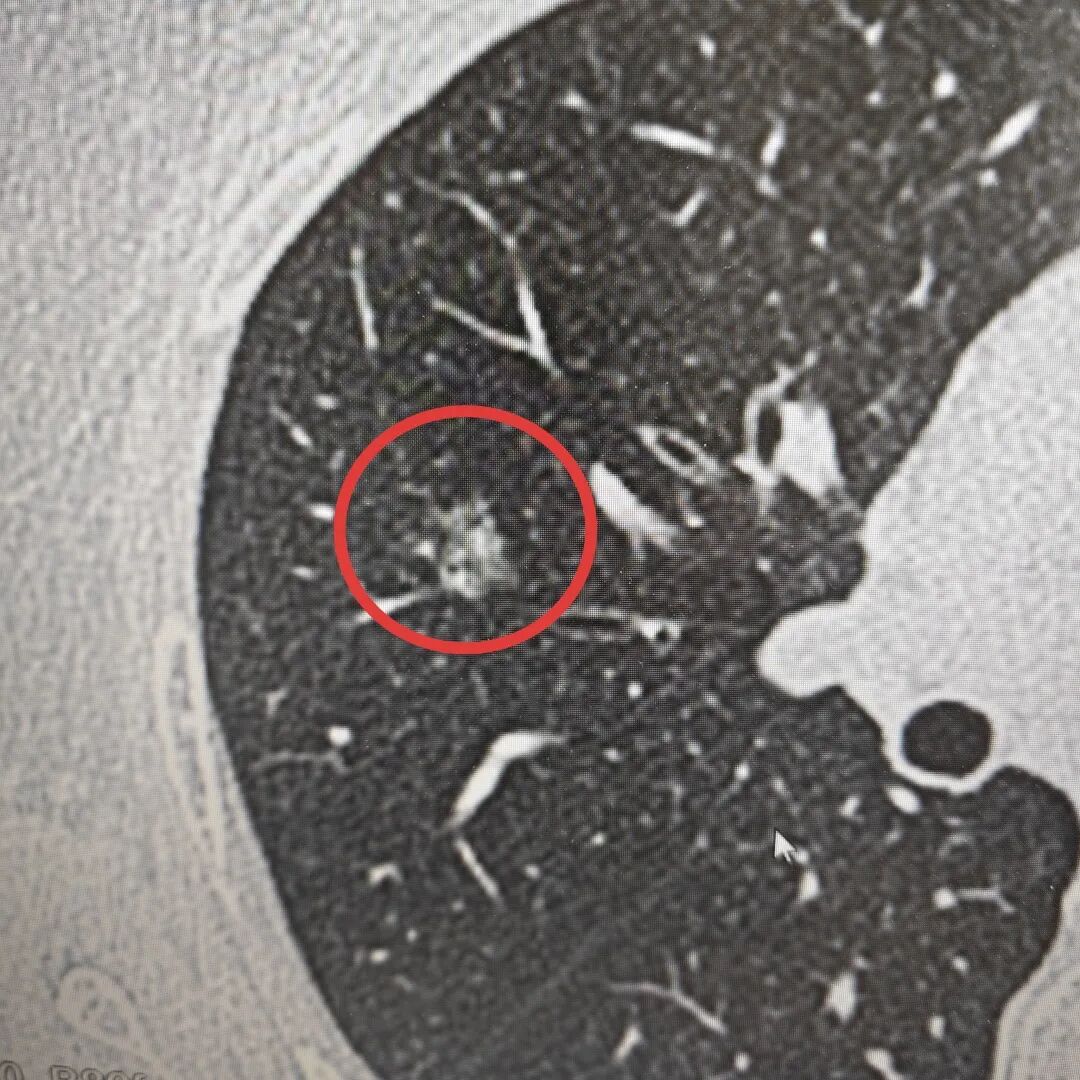

内容提要 >> “最初我们因肺结节多方求医,北京专家也曾倾向于良性病变,让我们一度放下心来。但葫芦岛二院孙振主任,凭借精湛的专业技术,敏锐地察觉出结节存在恶性风险(右肺上叶部分实性结节与右肺上叶磨玻璃结节),果断建议我们尽快手术治疗,为我们争取到了最宝贵的治疗时机……” 近日,市二院胸外科孙振教授团队收到一封情真意切的感谢信,这背后,是孙振教授靠着40年的临床经验,从看似“安全”的结节中,敏锐地发现了真正的风险。 半年前,患者体检时发现右肺上叶有个结节。家人不放心,专程去了北京,得到的诊断是“良性”。听到这个结果,全家人总算松了口气,决定先观察,定期复查。 今年1月,患者于我院复查胸部高分辨率CT(HRCT),结果显示:双肺多发大小不等结节,右肺上叶后段部分实性结节,大小约11mm×9mm,其内可见支气管影,周围伴有血管集束征;右肺上叶后段另见一枚约9mm×7mm的磨玻璃小结节。 孙振教授把患者历次影像资料反复对比,凭借几十年在胸外科一线积累的经验,敏锐判断这些结节恶性风险较高,建议尽快手术。他把自己的判断一五一十讲给患者和家人听,这份底气十足的诊断,最终让一家人选择留下来,在市二院接受手术。 手术由孙振教授主刀。术前先在CT引导下精准定位结节,术中采用胸腔镜微创技术进行肺段切除。术中冰冻病理结果很快出来:结节1是原位癌,结节2是浸润性腺癌,且结节2离切缘较近。孙振教授当即调整手术方案,改行右肺上叶切除,最大程度降低术后复发风险。 原位癌 浸润性腺癌 术后,在医护团队精心照护下,患者恢复顺利,仅5天便康复出院。一家人感激不尽,这才有了那封情真意切的感谢信和那面写有“妙手仁心医术高,德术双馨暖人心”的锦旗。 “……这无疑是最理想的手术结果。这份成功的背后,是您深厚的医学功底、严谨的诊疗态度,以及对患者生命高度负责的医者仁心。”一字一句,饱含着对孙振教授、马遇川医生、郭晨光护士长及胸外科全体医护人员的深深谢意与由衷认可,也生动诠释了“大病不离葫”这一民生承诺背后,最温暖、最坚实的力量。 孙振教授从事胸外科临床工作近40年,长期专注于肺结节、食管癌、肺癌等胸部疾病的精准诊疗,尤其在复杂食管癌根治术、胸腔镜微创手术等高端技术领域经验丰富,手术成功率高,患者长期生存质量显著提升。他用一双“火眼金睛”,为滨城百姓的肺部健康筑牢了坚实防线。 孙振 主任医师 三级教授 ·葫芦岛市第二人民医院胸外科主任、肺结节诊治中心主任 ·中国医科大学客座教授 ·原央企总医院著名胸外科专家 ·辽宁省医学会胸外科委员 ·辽宁省抗癌协会肺癌专业委员会委员 ·辽宁省细胞生物学学会食管癌专业委员会理事 ·主持多项科研成果,获科技成果奖、科技进步奖、国家专科奖项 医学成就:从事胸外科临床工作近40年,担任胸外科首席专家及科室主任20余年,是我省胸外科领军人物,推动肺癌、食管癌等胸部肿瘤外科的规范化诊疗,在央企总医院牵头成立了肺结节诊疗中心,率先开展CT引导下肺内小结节定位切除,既确切完整切除肺内小结节,又降低肺功能损害。 专业特色:擅长肺癌、食管癌的外科手术和综合治疗,在各类高难度胸外伤手术治疗、胸腔镜微创手术、胸腺瘤手术及复杂并发症处理方面具有高深造诣,尤其擅长肺癌早期诊断,胸部小结节CT早期肺癌的鉴别等。完成各类高难度胸外科手术5000余例,其中微创手术占比达90%,治愈率达98%,多项业务填补省内空白。 开展的高难手术包括:胸腔镜肺部结节微创手术、肺癌根治术、食管癌根治术、各种纵隔肿瘤切除术、胸骨后甲状腺手术及胸部复合性外伤的抢救手术等。 出诊时间:每周一、周二全天 出诊地点:门诊二楼著名专家诊区 咨询热线:16604299397